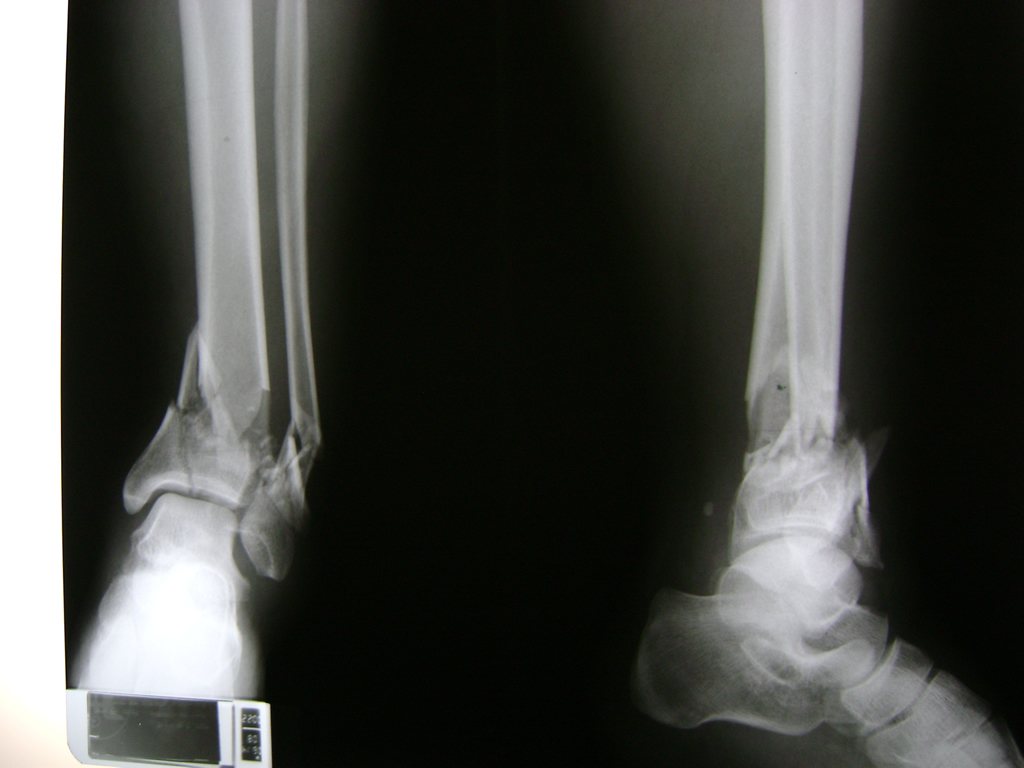

Una fractura de tobillo es la rotura de uno o más de los huesos del tobillo. Estas fracturas pueden ser:

- Parciales (el hueso está sólo parcialmente fisurado, no del todo).

- Completas (el hueso está perforado y está en 2 partes).

- Producirse en uno o ambos lados del tobillo.

Algunas fracturas de tobillo pueden requerir cirugía si:

- Los extremos de los huesos están desalineados entre sí (desplazados).

- La fractura se extiende hasta la articulación del tobillo (fractura intra-articular).

- Los tendones o ligamentos (tejidos que sujetan los músculos y los huesos entre sí) están rotos.

- El médico cree que sus huesos probablemente no sanen apropiadamente sin cirugía.

- El médico considera que la cirugía puede permitirle una recuperación más rápida y confiable.

- En los niños, la fractura involucra la parte del hueso del tobillo donde el hueso está creciendo.

Cuando se necesita cirugía, es probable que esta implique el uso de clavijas de metal, tornillos o placas para sostener los huesos en su lugar mientras la fractura se consolida. Los elementos de soporte pueden ser temporales o permanentes.